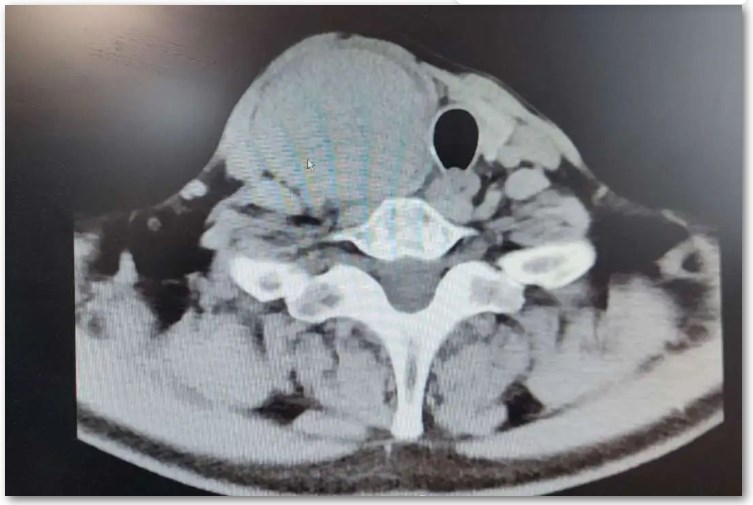

62歲的郝大叔半個月前無意間發(fā)現(xiàn)右側(cè)頸部有一包塊,呈雞蛋大小。隨即,郝大叔前往當(dāng)?shù)蒯t(yī)院進(jìn)行就診,經(jīng)檢查B超顯示右側(cè)葉囊性包塊,醫(yī)生告知只需讓包塊自行吸收??梢欢螘r間后,郝大叔發(fā)現(xiàn)包塊非但沒縮小,反而越長越大,還引起了頭疼。在了解了弟弟的情況后,郝阿姨立即帶他來到了西電集團(tuán)醫(yī)院灃東院區(qū)就診。 消化病區(qū)(普通外科)平勝醫(yī)生接診后,給郝大叔開具了相關(guān)必要檢查。增強(qiáng)CT檢查顯示:甲狀腺右側(cè)葉巨大囊性包塊,腫大約8x6x5厘米,需要手術(shù)。消化病區(qū)(普通外科)張家墉主任帶領(lǐng)外科團(tuán)隊(duì)對郝大叔的手術(shù)進(jìn)行了細(xì)致的術(shù)前討論,迅速制定出了手術(shù)方案。 入院第三天,郝大叔進(jìn)行了手術(shù),過程順利,術(shù)后安返病房。術(shù)后第一天,郝大叔就懷著激動的心情告訴醫(yī)護(hù)人員,“手術(shù)做得真好,我的頭疼癥狀減輕了,那個壓著我呼吸的‘包包’不見了,謝謝主任,謝謝平醫(yī)生!” 在郝大叔出院當(dāng)天,郝阿姨送來了一面錦旗,短短八個字,飽含著對科室全體人員的感謝和信任。